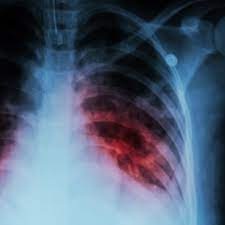

गरियाबंद । जिला प्रशासन की सक्रियता एवं स्वास्थ्य क्षेत्र में किये गये बेहतर कार्य से जिले के गांवों को महत्वपूर्ण सम्मान मिला है। भारत सरकार द्वारा जिले के 99 ग्राम पंचायतों को टीबी मुक्त पंचायत का दर्जा दिया गया है। यह उपलब्धि पिछले वर्ष जिला प्रशासन द्वारा चलाये गये टीबी मुक्त गरियाबंद अभियान के फलस्वरूप प्राप्त हुई है। इस अभियान के तहत जिले से टीबी को हराने के लिए घर-घर जाकर ढाई लाख से अधिक टीबी स्क्रिनिंग की गई थी। साथ ही 350 से अधिक निक्षय मित्र के रूप में आमजन, जनप्रतिनिधिगण एवं अधिकारी-कर्मचारियों ने भी टीबी मरीजों के सहायता के लिए भागीदारी सुनिश्चित की थी। सबके सफल सहयोग एवं प्रयास से जिले को बहुत बड़ी उपलब्धि मिली है। इस पर कलेक्टर श्री दीपक अग्रवाल ने खुशी जताते हुए स्वास्थ्य विभाग एवं जिलेवासियों को शुभकामनाएं दी है। उल्लेखनीय है कि वर्ष 2023 में भारत सरकार द्वारा टीबी मुक्त पंचायत अभियान चलाया गया था। इसका उद्देश्य टीबी को जड़ से मिटाना, टीबी मरीजों के प्रति संवेदनशीलता लाना तथा टीबी को हराने में सबका सहयोग सुनिश्चित करना था। इसके तहत टीबी को हराने विभिन्न गतिविधियों का संचालन किया गया था। साथ ही वृहद जनजागरूकता अभियान चलाया गया था। इसी तारतम्य में गरियाबंद जिले में भी टीबी मुक्त अभियान चलाया गया। इसके तहत घर-घर जाकर टीबी संदिग्ध लोगों के सैम्पल लिये गये थे। इसके तहत ढाई लाख से अधिक स्क्रिनिंग की गई। इस दौरान 344 से अधिक टीबी संदिग्ध लोगों का सैंपल भी लिया गया, जिसमें से बहुत कम टीबी मरीजों की पुष्टि हुई थी। जिला प्रशासन द्वारा जनप्रतिनिधियों, गणमान्य नागरिकों, सामाजिक, व्यापारिक, राईस मिलर्स संगठनों, अधिकारी-कर्मचारियों सहित अन्य लोगों को प्रेरित कर टीबी मरीजों के सेहत में सुधार लाने के लिए उन्हें निक्षय मित्र बनने के लिए प्रेरित किया गया था। इसके तहत 350 से अधिक लोगों ने निक्षय मित्र बनकर टीबी मरीजों को टीबी से उबरने में सहायता की। साथ ही टीबी मरीजों को पोषण किट का भी वितरण किया था, जिससे टीबी मरीजों को टीबी बीमारी से उबरने में मदद मिली। भारत सरकार द्वारा टीबी मुक्त पंचायत का दर्जा पाने वाले ग्राम पंचायतों में रानीपरतेवा, कसेकेरा, अमलोर, जामली, पाटसिवनी, खैरझिटी, करकरा, पक्तियाँ, मुरमुरा, फुलझर, पोंड, सिवनी, टेंगनाबासा, सेम्हारा, दादरगांव नया, रसेला, द्वारतरा, करचाली, मोंगरा, दादरगांव पुराना, टोनहीडबरी, कुटेना, लोहझर, गिरसूल, मोखागुड़ा, फालसापारा, कुम्हड़ईखुर्द, लाटापारा, कोदोभाटा, सुकलीभाटा पुराना, दर्लीपारा, सितलिजोर, झिरीपानी, निस्टिगुडा, दहीगांव, पुरनापानी, खुटगांव, घोघर, कदलीमुड़ा, सिनापाली, रोहनागुड़ा, बहेराबुड़ा, कोदोबदत, कस, घुटकू नवापारा, बारबहारा, कौंदकेरा, फुलकर्रा, पीपरछेड़ी कला, मौहाभाठा, लोहारी, गुजरा, मरोदा, बेंदकुरा, बिन्द्रानवागढ़, खुर्सीपार, खरता, मोंहदा, देहारगुड़ा, मैनपुरखुर्द, शोभा, गोपालपुर, गरहाडीह, कोकड़ी, खजूरपदर, ढोढरा, भेजीपदर, छोटेगोबरा, दबनई, मैनपुरकला, तौरेंगा, भूतबेड़ा, कुचेंगा, धनोरा, चलनापदर, उरमाल, धरनीधोरा, सोनेसिल्ली, पेंड्रा, जामगांव, रजकट्टी, कुम्ही, धमनी, बरूला, चौबेबांधा, श्यामनगर, कोपरा, धुरसा, रवेली, कुंड, चरोदा, चारभट्ठी, बोड़की, परसदाजोशी, गुंडरदेही, खुटेरी, पोखरा, पितईबंद एवं ग्राम पंचायत रोहिना शामिल है।

99 पंचायतों को भारत सरकार से मिला टीबी मुक्त पंचायत का दर्जा… घर-घर जाकर ढाई लाख से अधिक की गई थी स्क्रीनिंग